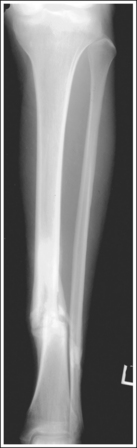

Image density is uniform across the lower leg.

The lower leg demonstrates a lateral projection. The distal fibula is superimposed by the posterior half of the distal tibia. The fibular midshaft is free of tibial superimposition. The tibia is partially superimposed over the fibular head, and the medial femoral condyle is demonstrated posterior to the lateral condyle if the leg is extended; the condyles are superimposed if the knee is flexed at least 30 degrees (compare Figure 6-67 and Image 51).

The tibial midshaft is at the center of the exposure field. The tibia, fibula, ankle, knee, and surrounding lower leg soft tissue are included within the collimated field.

• A perpendicular central ray is centered to the midpoint of the lower leg to demonstrate the tibial midshaft in the center of the image.

• To include the ankle and knee joints on the image, you must consider the degree of x-ray beam divergence that occurs when a long body part is imaged (see Figure 6-66). A 14- × 17-inch (35- × 43-cm) detailed screen-film or computed radiography IR should be adequate to include both the ankle and knee. When a screen-film system is used, the leg can be positioned diagonally to accommodate the length. For the computed radiography system, it is not advisable to do this unless the system is set to handle this alignment. To ensure that both joints are included, the IR should extend 1 inch (2.5 cm) beyond each joint space. The ankle is located at the level of the medial malleolus, and the knee is located 1 inch (2.5 cm) distal to the palpable medial epicondyle.